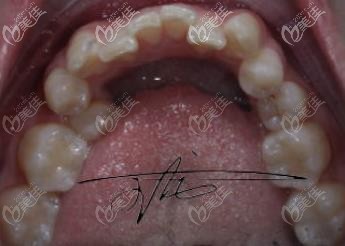

术前照片:

都说貌美齿为先,我这一口大龅牙可是为我的颜值拉了不少分,不过好在,我在雅莱做了陶瓷半隐形矫正,别问我为什么不选隐形矫正(贫民窟女孩的痛苦)!现在看来貌似效果还不错哦,分享给大家吧!

当时去的时候正好他们的王院长在,那我这肯定想找更专业的医生来看了!当时面诊后说我这个是龅牙,而且牙齿过于拥挤,需要拔牙,我还挺害怕拔牙的,就说我先考虑考虑!

给大家看看我矫正牙齿前后的对比吧~希望大家能替我开心,也祝大家都有一口整齐的牙齿!